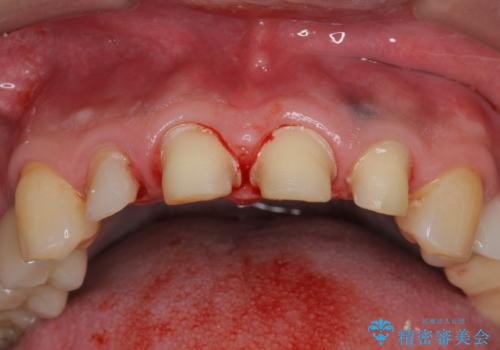

- 前歯の虫歯に気付きながらも放置し、一念発起し治療を希望され来院されました。

虫歯のマイクロスコープによる丁寧な除去、根管治療、深い虫歯に対する挺出(エクストリュージョン)および歯周外科を行ったのち精度の高いセラミッククラウン製作治療を計画します。

虫歯の放置により、根管治療や深い虫歯に対する処置が必要になりましたが丁寧に一つづつ処置を行ったことで抜歯をすることなく歯を残すことができました。

セラミッククラウンの製作をする前に、歯内・歯周環境の整備は非常に大切です。